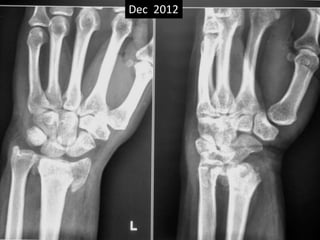

Case one

• 42 years old female.

• Low energy trauma.

• Fracture lower end radius

• Treated conservatively by closed reduction

and pop casting in Dec 2012.

Dec 2012

Case one •42 years old female. • Low energy trauma. • Fracture lower end radius • Treated conservatively by closed reduction and pop casting in Dec 2012.

• 13.

March 2013 Closereduction and POP Early sign